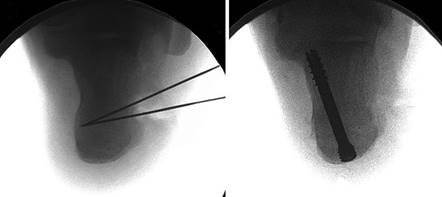

To achieve multiplanar correction, the surgeon must address the sagittal, coronal, and transverse planes. The first metatarsal is plantarflexed to restore the longitudinal arch, rotated out of pronation to realign the sesamoids, and translated laterally to close the IMA. Subchondral drilling or feathering is performed to optimize the biological environment for fusion. Fixation is traditionally achieved with two or three crossed solid or cannulated screws (typically 3.5mm or 4.0mm). Recently, plantar or medial locking plates have gained immense popularity due to their superior biomechanical construct, allowing for earlier weight-bearing. Bone graft or orthobiologics may be packed into the arthrodesis site to stimulate osteogenesis.

Positioning of the fusion is the most critical step of the operation. The hallux must be positioned in 10-15 degrees of valgus, 15-20 degrees of dorsiflexion relative to the first metatarsal, and neutral rotation. Excessive dorsiflexion causes shoe impingement, while insufficient dorsiflexion leads to vaulting during gait and interphalangeal joint arthritis. Fixation is most reliably achieved using a pre-contoured dorsal locking plate combined with a lag screw crossing the fusion interface.

Clinical & Radiographic Imaging Archive